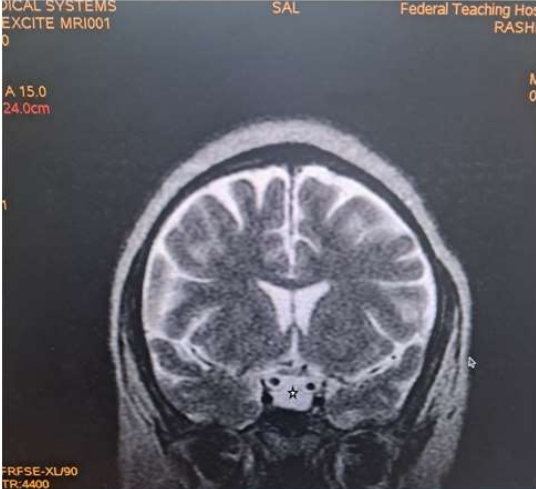

Magnetic Resonance Imaging (MRI) revealed expansion of the sella with a well-defined fairly rounded lesion measuring 15 X 14 X 15mm (width X AP X H). It is hypointense on T1W, hyperintense on T2W and suppressed on FLAIR sequence. Rim enhancement is seen post contrast. The mass is inseparable from the optic chiasma suggestive of compression.

Figure 7: Coronal T1W image of the brain showing a hyperintense rounded intrasellar mass lesion (black asterisk).

Due to its high soft tissue resolution, Magnetic Resonance Imaging (MRI) is the primary diagnostic technique for RCC9. It also determines the cystic content and fluidity of the cyst which is useful in planning for subsequent patient’s management10. Fifty percent are hyperintense on T1W (due to high protein content) while 50% are hypointense. On T2W, 70% are hyperintense, 30% iso or hypointense and 20% have hypointense rim. T1W Post contrast images usually show no enhancement. However, a thin enhancing rim may be seen when cyst wall infection is present [19-20]. The case presented revealed expansion of the sella with a well-defined fairly rounded lesion measuring 15 X 14 X 15mm (width X AP X H). It is hypointense on T1W, hyperintense on T2W and suppressed on FLAIR sequence. Rim enhancement is seen post contrast. The mass is inseparable from the optic chiasma suggestive of compression. The appearance of the cyst confirmed no haemorrhage or debris within the cyst. However, the rim enhancement suggest inflammation of the cyst as explained in the text. The finding of optic chiasma compression may explain the visual impairment and the bitemporal hemianopia seen in the patient.